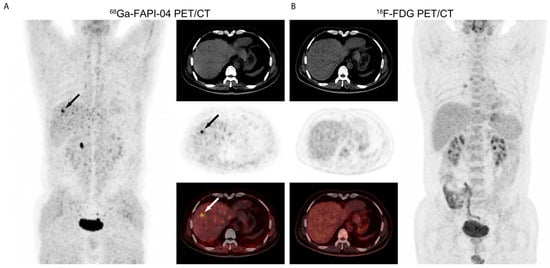

- Wang, H.; Zhu, W.; Ren, S.; Kong, Y.; Huang, Q.; Zhao, J.; Guan, Y.; Jia, H.; Chen, J.; Lu, L.; et al. 68Ga-FAPI-04 Versus 18F-FDG PET/CT in the Detection of Hepatocellular Carcinoma. Front. Oncol. 2021, 11, 693640. [Google Scholar] [CrossRef] [PubMed]